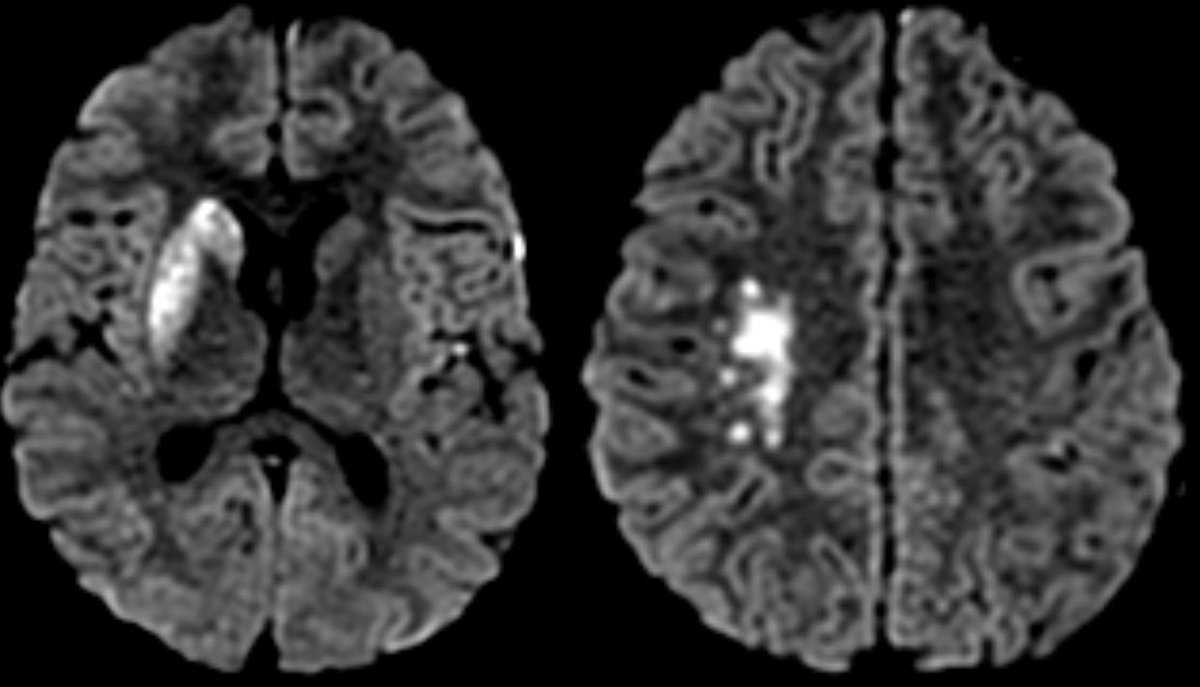

▶️CT-: Subtle loss of GW in the right caudate nucleus

▶️CTA: Severe spasm of right ICA terminus and MCA and to a lesser degree, the left side as well

▶️CT perfusion: elevated Tmax in the bilateral (right greater than left MCA territories)

Of note, caution must be taken when interpreting CT perfusion in peds patients if the injection rates are slower than those used in adults (can mess with transit times)

▶️Spasm was confirmed on angio in the right ICA terminus and MCA (greater than left) …treated with verapamil

MR shows the extent of the core infarct involving the right BG and MCA-ACA border zone (watershed)